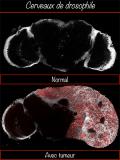

L’équipe de Cédric Maurange à l’Institut de biologie du développement de Marseille (IBDM) démontre qu’une horloge moléculaire, active dans les cellules souches neurales au cours du développement de la drosophile, détermine quelles cellules filles pourraient donner naissance à des tumeurs cancéreuses en cas de dédifférenciation. Les chercheurs identifient un réseau de gènes dont la perturbation pendant le développement confère des propriétés prolifératives illimitées. Ces travaux publiés dans la revue eLife, ouvrent la voie à une compréhension des mécanismes de l’agressivité des tumeurs cérébrales pédiatriques précoces.